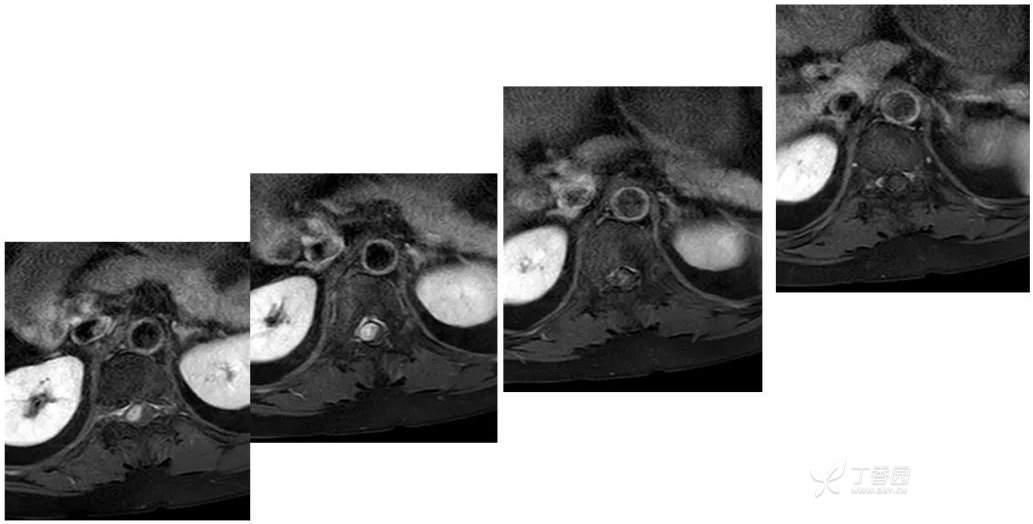

MR: